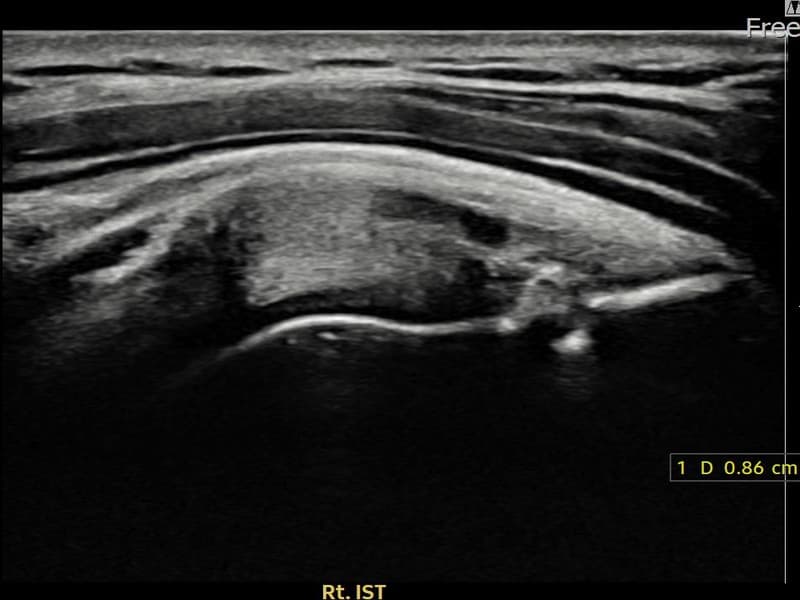

超声确认右侧 冈下肌腱 附着部部分撕裂(8.6mm × 4mm (肌腱厚度约45%缺损))。缩小缝合术后肌腱连续性恢复,患者回归正常生活。

术前超声确认右侧 冈下肌腱 附着部部分撕裂,右侧冈下肌腱回声不连续伴肌腱缺损(8.6mm × 4mm (肌腱厚度约45%缺损))。术后超声显示撕裂部位充满再生组织,肌腱连续性恢复,回声模式正常化。

该患者持续肩痛。详细超声检查确认右侧 冈下肌腱 附着部部分撕裂(缺损:8.6mm × 4mm (肌腱厚度约45%缺损))。在超声引导下实施非手术缩小缝合术。术后佩戴支具约4-6周,随后进行分阶段康复锻炼。随访超声确认肌腱连续性恢复、结构稳定,患者顺利回归日常生活。